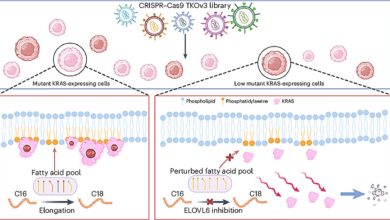

Studie, Publikováno v Journal of the National Cancer Institutezjistili, že AI byla schopna identifikovat „mamograficky viditelné“ typy intervalových rakovin dříve tím, že je v době screeningu označila. Patří mezi ně nádory, které jsou viditelné na mamogramech, ale nejsou detekovány radiology, nebo mají velmi jemné známky mamografie, které lze snadno vynechat, protože znaky byly slabé nebo pravděpodobně pod úrovní detekce lidským okem.

Radiologové poté tyto případy přezkoumali, aby určili, proč rakovina nebyla spatřena dříve. Nová studie přizpůsobila evropský klasifikační systém kategorizaci intervalových rakovin. Zahrnují: zmeškané chyby čtení, minimální znaky – působící, minimální znaky – ne – ne – nekomplikovatelné, skutečná rakovina intervalu, okultní (což je na mamogramu skutečně neviditelné) a kvůli technické chybě zmeškané.

Vědci poté použili komerčně dostupný software AI s názvem Transpara na počáteční screeningové mamogramy provedené před Diagnóza rakoviny Chcete -li zjistit, zda by to mohlo detekovat jemné známky rakoviny, které byli radiologové vynecháni během počátečních projekcí, nebo je alespoň označili jako podezřelé. Nástroj skóroval každý mamogram od 1 do 10 pro riziko rakoviny. Skóre 8 nebo vyšší bylo považováno za označené jako potenciálně.